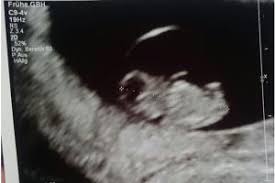

Seine Extremitäten wachsen und an den Händen und Füßen sind. Erstmals konnten sie auf dem Ultraschallmonitor ihr Kind und sein kleines schlagendes Herz sehen. Das Baby schlägt nun Purzelbäume zappelt und schwimmt in der Fruchtblase. Die Anlage der Ohren ist jetzt zu erkennen. Enjoy the videos and music you love upload original content and share it all with friends family and the world on YouTube. Der Kiefer ist nun entwickelt. Auch die Nasenöffnung und die Ohren sind in der 9. Die Augen sind mit Augenlidern bedeckt. SSW Baby Mama Untersuchung.

Die Beine sind länger geworden und in der 9. Schwangerschaftswoche steht die erste große Vorsorgeuntersuchung mit Ultraschall an. Schwangerschaftswoche fällt es vielen Vätern leichter sich auf die veränderte Lebenssituation einzulassen. Die SSL Scheitel-Steiß-Länge beträgt nun 1722 mm. Der Kiefer ist nun entwickelt. Dabei wird das Baby erstmals ausführlich im Ultraschall vermessen. Dieser Zeitraum ist überaus wichtig für die Entwicklung der Arme und Beine.